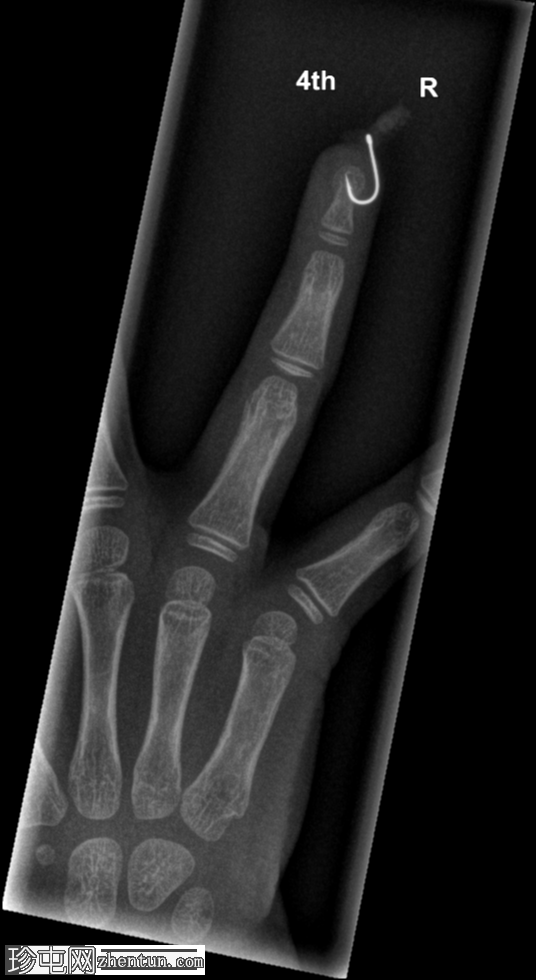

右手无名指

X光片

正位片

鱼钩异物,附有蛆虫。

鱼钩异物较为常见,但像本例中鱼钩上还附着蛆虫的情况则较为罕见!